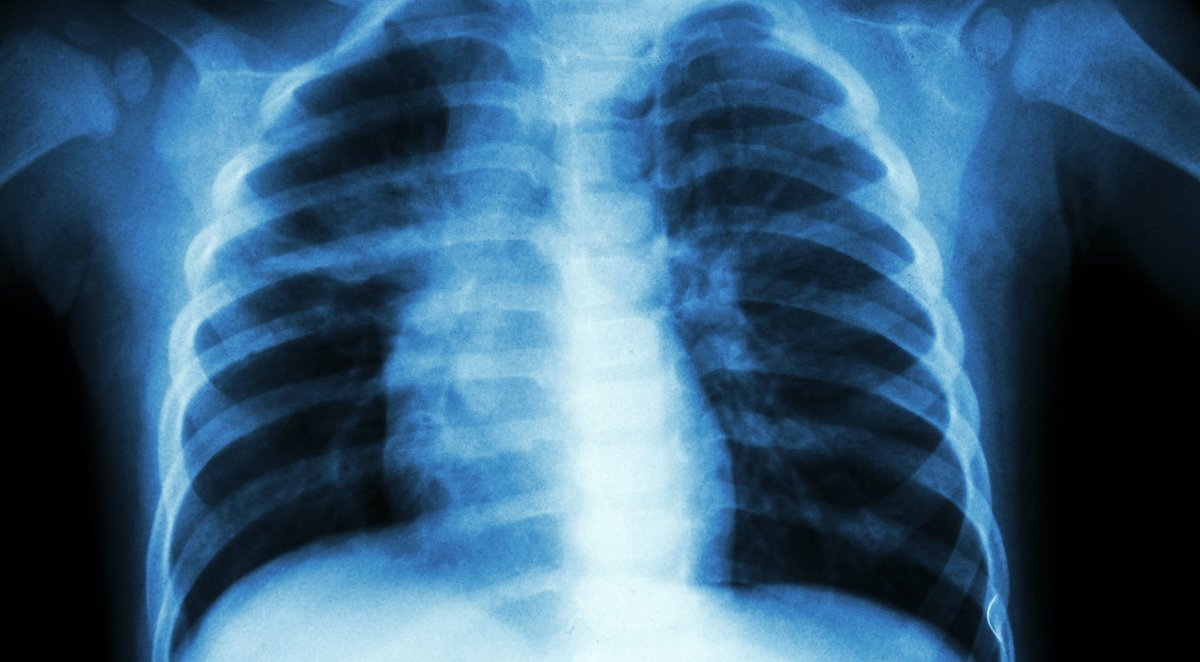

Plaučių vėžys gali pasireikšti 2 simptomais akyse

Amerikos vėžio draugijos teigimu, ne visi plaučių vėžio simptomai sukelia plaučių problemas – du jų gali pasireikšti akyse. Navikai gali paveikti tam tikrus akies nervus ir dalį veido, sukeldami vadinamą Hornerio sindromą.

Sindromas gali pasireikšti akies voko užkritimu ant akies, taip pat tos akies vyzdys gali būti mažesnis. Dar vienas simptomas – prakaitavimas toje pačioje veido pusėje. Pastebėjus šiuos simptomus, raginama nieko nelaukiant apsilankyti pas gydytoją.

Į gydytoją taip pat turėtumėte nedelsiant kreiptis, jei pasireiškia tokie simptomai kaip nuolatinis kosulys ar dusulys, atkosėjimas krauju.

Kiti plaučių vėžio požymiai apima nepaaiškinamą nuovargį ar svorio kritimą, skausmą kvėpuojant ar kosint.

Kuo anksčiau nustatomas plaučių vėžys, tuo daugiau šansų jį sėkmingai išgydyti, rašo portalas express.co.uk.